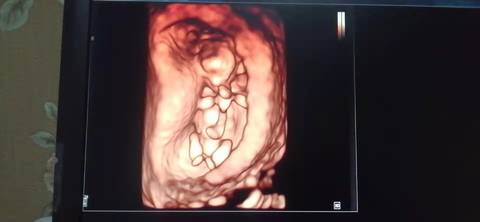

十二周的nt,是不是小棉袄啊? 医生给看宝宝腿的时候生殖器那里是平平的,是女宝吗?我和老公都挺想要小棉袄的

journal_insert_pic_1741079939journal_insert_pic_1741080157journal_insert_pic_1741080307

你好,我们是看不出来的,只要是健康的宝宝,都是上帝赐予的礼物,孕期定期检查,祝心想事成 。